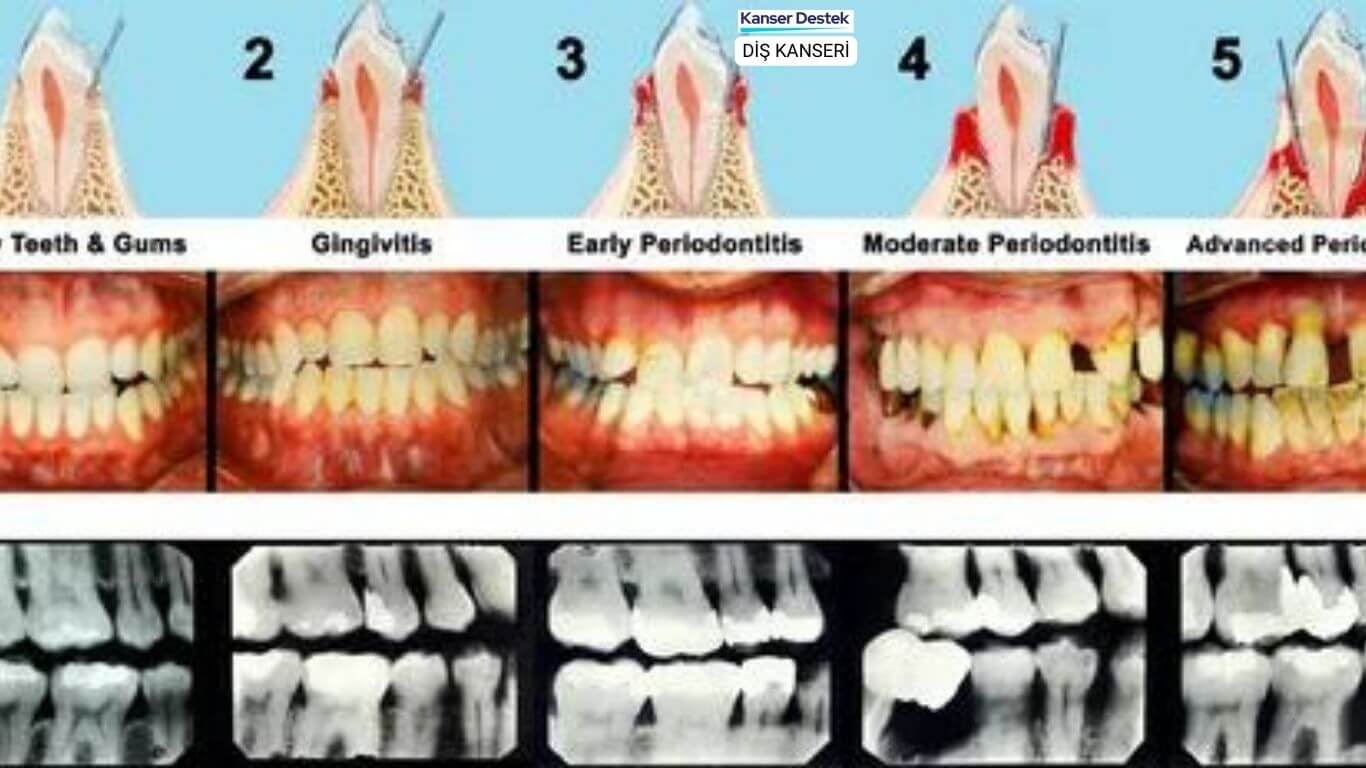

8 Diş Kanseri Belirtisi ve Özel Tedavi Yöntemleri